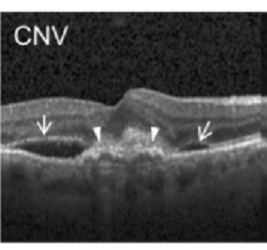

Classifying Retinal OCT Images

Can we detect Retinal Disorders in OCT images using CNNs?

Challenges: Occasional poor image quality, differing image heights and widths, unbalanced classes

Methods Applied: Filters to reduce noise, fixed image pixel sizes, balancing classes, and training with blocks of 1000 images at once

Utilities: Python, Keras, Tensorflow 2.0, OpenCV, CNNs, Pretrained and custom models

Result:  Achieved a 97% testing accuracy on average with 5-fold cross validation with pretrained models on a class-balanced dataset. Training time reduced by 80% compared to a traditional non-pretrained CNN modeling approach.